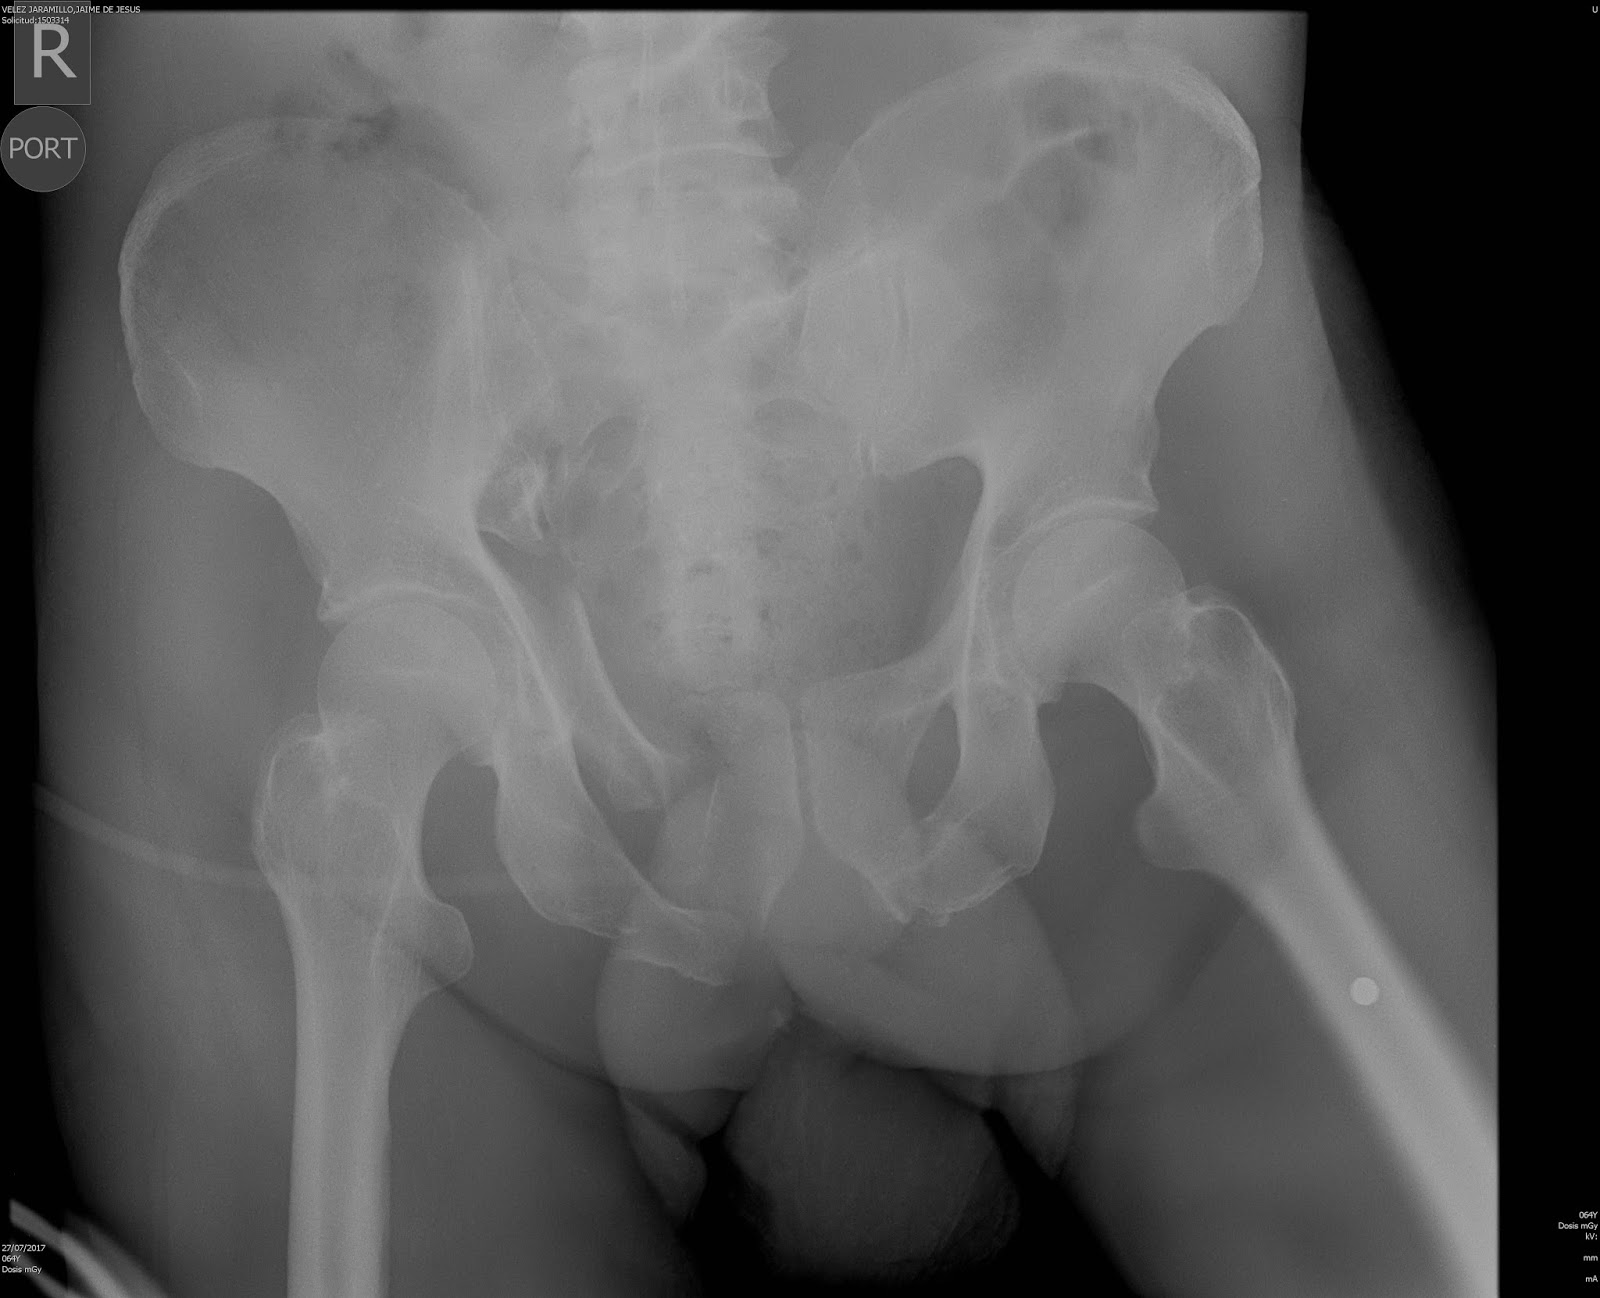

Ortopedia Adultos: 2017

Fractura de fémur - Wikipedia, la enciclopedia libre

Miembro Inferior \u2013 Instituto de Ortopedia y Traumatología